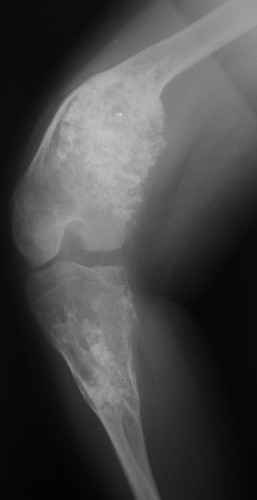

Диагноз: Дисхондроплазия. Варусная деформация дистального метафиза правой бедренной кости; состояние после оперативных вмешательств (1993 и 1994 гг.).

Деформация правой нижней конечности с 6 месяцев (стала прогрессировать после года, с момента начала ходьбы). Поставлен диагноз болезнь Олье, варусная деформация, укорочение правой нижней конечности на 4,5 см. 1993 г. - операция остеоклазия на уровне очагов поражения в н/3 правой бедренной кости и в/3 правой большеберцовой кости с одномоментной коррекцией деформации и фиксацией костных фрагментов спицами Киршнера. После начала статической нагрузки (1994 г.) появился рецидив деформации и укорочения. Вторая операция - ЧКО АВФ, аппарат демонтирован через 2 недели в связи с развившимся на уровне стержня переломом, после чего находилась в гипсовой повязке до консолидации костных фрагментов. Далее лечилась консервативно в гипсовой повязке. Выраженная деформация и укорочение правой нижней конечности. Относительная длина бедер: справа - 34 см, слева - 51 см; анатомическая длина голеней: справа - 29 см, слева - 39 см. Величина варусной деформации на уровне дистального отдела правого бедра составляет - 80 град. Амплитуда движений в коленных суставах (разгибание/сгибание ): справа - 0/0/100 град.; слева - 0/0/30 град. Отмечается боковая и ротационная нестабильность на уровне правого коленного сустава. Амплитуда движений в голеностопных суставах - в норме. Тактика лечения? Заранее благодарю! С уважением, А.В.Владзимирский